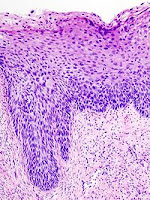

Neoplastik değişiklikler skuamokolumnar bileşkeden (junction) başlar. Serviks kanseri gelişmesinde serviks epitelinde birbiri ardısıra gelen değişiklikler olur, bu da serviks kanserinin erken tanısında önem taşır.

Bu değişiklikler sırasıyla:

1. Normal endoservikal kolumnar epitel

2. Skuamöz metaplazi

3. Hafif-orta-ağır displazi

4. Karsinoma in situ

5. Mikroinvazif karsinom

6. Belirgin invazif karsinom, şeklindedir.

Premalign lezyonların evrelendirilmesi

Preinvaziv servikal hastalık kavramı, 1947 senesinde invaziv kanser görünümüne sahip ancak epitelle sınırlanan epitelial değişiklikler tanımlandığında ortaya atılmıştır. Displazi ve CIS’ın (Karsinoma in situ) sürekli bir olayın farklı basamaklarını teşkil ettiğini düşünen Richart, 1967 yılında servikal intraepitelial neoplazi (CIN I, II, III) terimini tanımlamıştır. Sonraki çalışmalar bu lezyonların tedavi edilmemeleri halinde servikal kansere yol açabileceğini gösterdi. Şimdi ise tedavi edilmediği zaman erken CIN lezyonlarının çoğunun eş zamanlı olarak gerilediği bilinmektedir. Günümüzde anormal lezyonların gelişiminde premalign displastik değişikliklerin değerlendirilmesi için CIN sistemi kullanılmaktadır.

Servikal intraephitelial neoplazi (CIN):

* CIN I Hafif displazi (atipik hücreler epitelin alt 1/3’ünde sınırlı)

* CIN II Orta displazi (atipik hücreler epitelin alttan 2/3’lük kısmında ise)

* CIN III Ağır displazi (epitelin tamamına yakını tutulmuş ise)

* CIS Karsinoma in situ (epitelin tamamı tutulmuşsa)

Not I: CIN I düşük evreli skuamöz intraepitelyal lezyon; CIN II/III yüksek evreli skuamöz intraepitelyal lezyon olarak da isimlendirilir.

Not II: Bütün lezyonlarda bazal membran sağlamdır.

İnvaziv servikal kanserler genellikle uzun bir preinvaziv hastalık evresini izlerler. Mikroskopik olarak, invaziv karsinomlara ilerlemeden önce hücresel atipiden, değişen derecelerde servikal intraepitelyal neoplazilere (CIN) ilerleyen prekürsor lezyonlar spektrumu ile karakterizedir. CIN I lezyonlarının büyük çoğunluğunun geçici olduğu; kısa dönemlerde normale gerilediği veya yüksek derecelere ilerlemediği iyi bilinmektedir. Diğer taraftan, yüksek dereceli (CIN II, III)’ler, her ne kadar bu tür lezyonların da bir kısmı gerilese de, yüksek oranda invaziv kansere ilerleme olasılığı taşır. Servikal öncü lezyonların invaziv kansere ilerlemesinin ortalama 10 ila 20 yıl kadar uzun bir zaman aldığı bilinmektedir.